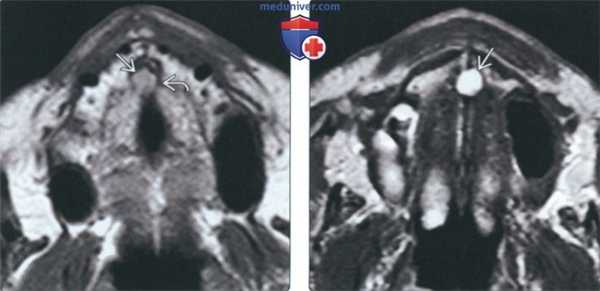

5. МРТ при кисте носонебного протока:

• Т1 ВИ:

о Однородный изо- или гиперинтенсивный сигнал

• Т2 ВИ:

о Однородный гиперинтенсивный Т2 сигнал

• Контрастное усиление обычно отсутствует:

о Воспалительный компонент может накапливать контраст

(Слева) На аксиальной МРТ (Т1 ВИ) определяется вздутие резцового канала с промежуточным - слегка гиперинтенсивным Т1 сигналом, обусловленное КННП. Обратите внимание на истонченную, но в остальном сохранную кортикальную пластинку.

(Справа) На аксиальной MPT (Т2 ВИ) определяется классическая КННП. Обратите внимание на срединное округлое включение с однородным гиперинтенсивным Т2 сигналом в верхней челюсти.

4. МРТ при кисте носонебного протока:

• Т1 ВИ: равномерно изо- или гиперинтенсивный сигнал, Т2 ВИ: гиперинтенсивный сигнал

• Обычно не накапливает контраст:

о Накопление контраста связано с воспалением

(Слева) При МРТ Т1ВИ в аксиальной проекции определяется расширение резцового канала со слегка гиперинтенсивным сигналом, обусловленное кистой носонебного протока. Обратите внимание на сохранный, но истонченный кортикальный слой.

(Справа) При МРТ Т2ВИ в аксиальной проекции визуализируется киста носонебного протока, имеющая «классический» вид. Киста выглядит как округлое гиперинтенсивное образование верхней челюсти, имеющее однородную структуру и располагающееся по средней линии.